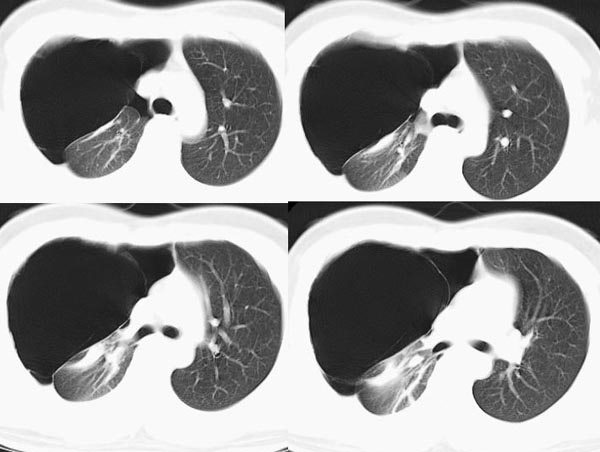

m21y既往体健,否认结核、支扩等病史;1周前患上感,无明显咳嗽,自觉无明显不适。单位体检透视时发现右侧液气胸!cr及ct如下(肺组织窗:l:-598hu w:1132hu):请大家会诊!!

右侧巨大含气囊性病变,壁薄、光整、其外侧见气体。右肺压迫性肺不张、胸腔内见少量积液。纵隔向左侧移位。左肺未见异常。诊断:1.右侧含气肺囊肿(先天性)。2.右侧液气胸。(少量液体)3.右肺压迫性肺不张。我也遇见一例这样的病人。女性。股骨外伤就诊。常规胸片发现右侧囊性病变。